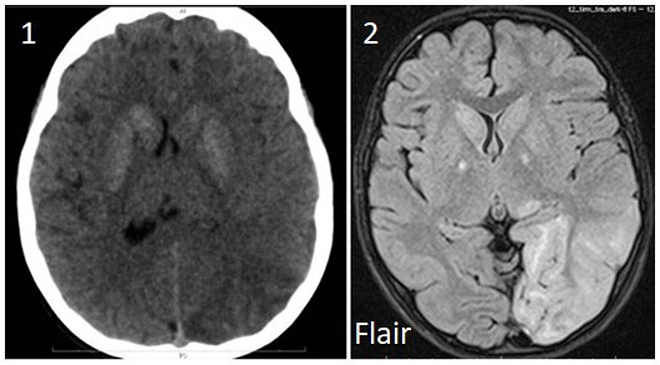

по данным КТ ГМ предположен герпетический энцефалит (посмотреть фото);

МРТ ГМ: см. рис.2

Нейровизуализация (частые признаки):

КТ: кальцификаты базальных ганглиев

МРТ: очаги усиления сигнала в режимах Т2/ FLAIR (чаще в задних отделах мозга, не совпадающих с зонами васкуляризации крупных сосудов)

При использовании метода DWI (диффузно-взвешенные изображения) коэффициент диффузии повышен, в отличие от снижения при ишемическом инсульте

КТ ГМ предположен герпетический энцефалит